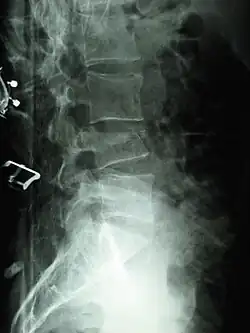

Las fracturas por compresión generalmente se diagnostican en las radiografías de la columna vertebral, donde una vértebra con forma de cuña puede ser visible o puede haber pérdida de altura de la vértebra. Además, la medición de la densidad ósea se puede realizar para evaluar la osteoporosis. Cuando se sospecha que un tumor es la causa subyacente o si la fractura fue causada por un traumatismo grave, se pueden realizar tomografías axiales computarizadas o resonancias magnéticas.